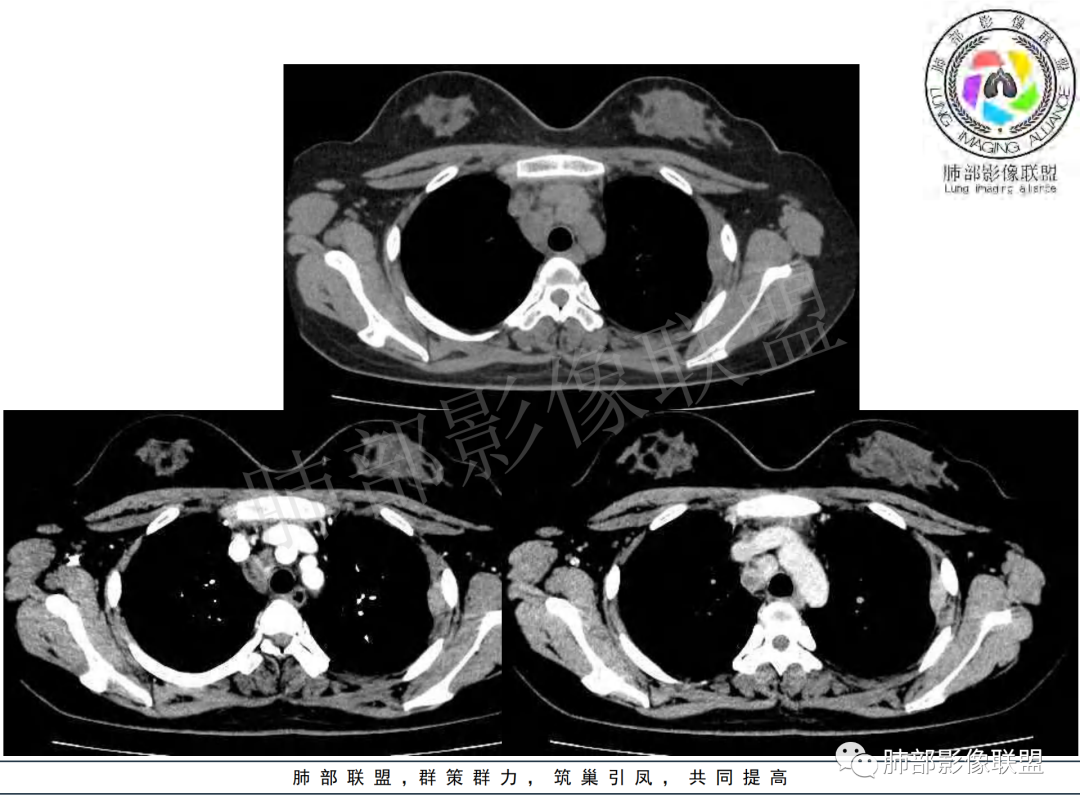

右肺肺门旁肿块,右肺中间段支气管腔内结节,增强强化不均;纵隔多发淋巴结环形强化,右侧少量胸腔积液,临床发热入院,考虑结核,鉴别肿瘤。

纵隔多组及右侧肺门多发肿大淋巴结,部分融合,不均匀强化,内见斑片状坏死区及环状强化,后者坏死边界尚清晰,肺门区肿大淋巴结与肺组织边界不清,年轻女性,8个月病史,发热首发症状,考虑淋巴结核并向肺内侵及(破溃?),鉴别淋巴瘤

女,20,病程长达8月,发热、胸痛、右侧胸腔积液病史。胸部CT:右肺门旁不规则肿块影,右中间支气管腔内结节,纵隔多发淋巴结肿大;强化不均匀,灶性坏死灶,环形强化;右侧少量胸腔积液并局部肉芽肿样突起。年轻女性,长病程,多部位,考虑慢性炎症,结核?鉴别肿瘤。

年轻女性,慢性病程,发热、胸痛。右肺门旁不规则肿块影,纵隔多发淋巴结肿大;强化不均匀,环形强化;右侧少量胸腔积液;首先考虑结核,鉴别肿瘤,结节病。

慢性病程,前纵隔右肺门旁多发淋巴结肿大;强化不均匀,环形强化;右侧少量胸腔积液;考虑结核,鉴别结节病。

青年女性,发热、胸痛、右侧胸腔积液病史,病程8个月。曾多次抗炎后均有好转。CT:右肺门旁肿块影,双侧胸膜结节,纵隔多发淋巴结肿大,边缘模糊;增强渐进性明显强化,纵膈淋巴结较彻底坏死灶,边缘环形强化。考虑结核,鉴别恶性肿瘤。

女性,20岁。高热、畏寒。右肺上叶近肺门区不规则肿块,周围斑点、片小结节影伴肿大淋巴结,肿块包绕并突入右主支气管腔内,增强后肿块不均匀强化,淋巴结环形强化中心低密度,考虑结核。

本例患者,年轻女性,慢性病程,多次抗感染治疗效果不佳,实验室检查示白细胞及中性粒细胞不高,不支持普通细菌感染,虽然肺泡灌洗液X-Pert检测阴性,结合患者胸部CT结核感染亦不能排除,胸部CT主要表现为右侧肺门及纵隔淋巴结肿大,仔细观察不难发现右中间支气管内新生物凸向管腔内,增强扫描,右肺门(10R)及纵隔淋巴结(2R,4R)明显不均匀强化,内部呈不规则低密度无强化区,被周边高强化区包绕(环形强化)的特点,首先应当想到纵隔淋巴结结核诊断。淋巴结分布亦不符合肺部恶性肿瘤迁徙途径。